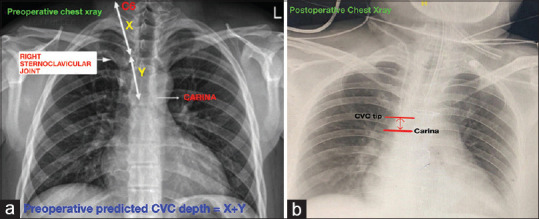

Materials and methods: One hundred patients aged between 18 and 65 years undergoing elective cardiac surgery were enrolled in the study. In the operation room, under ultrasound guidance, right internal jugular vein was punctured and CVC was inserted. The primary outcome was to determine the accuracy of placing the CVC tip under TEE guidance at the SVC-RPA junction by intraoperative surgical palpation and to correlate between the preoperative chest radiograph-predicted CVC depth and the TEE-guided placement of CVC depth. The secondary outcomes were to evaluate the position of CVC tip in relation to the carina in postoperative chest radiograph and the incidence of complications.

Results: A total of 98 patients were included in the analysis. The CVC tip was palpable by the surgeon intraoperatively at the SVC-RPA junction in 76 patients (77.6%). A significant direct correlation was observed between the predicted preoperative CVC depth and TEE-guided placement of CVC depth (r = 0.7441, P < 0.0001). In the postoperative chest radiograph, 78 (79.5%) patients had the CVC tip positioned above the carina. Twenty-nine patients had atrial ectopics and six patients had ventricular ectopics during CVC insertion.